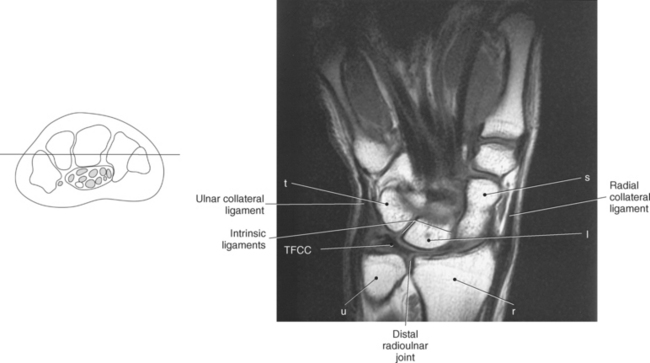

The joints of the wrist and hand are quite complex and consist of the following: distal radioulnar articulation, radiocarpal articulation (proximal joint of hand), midcarpal articulation (distal joint of hand), intercarpal articulations (articulations between proximal and distal carpals), carpometacarpal articulations (between carpals and metacarpals), the intermetacarpal articulations (between bases of metacarpals two through five) and the interphalangeal joints (between phalanges of each digit) (Figures 9.111 and 9.115). The distal radioulnar articulation, also called the distal radioulnar joint (DRUJ), is created when the ulnar notch of the radius moves around the articular circumference of the ulna, providing the movements of supination and pronation. The main stabilizing element of the DRUJ is an articular disk called the triangular fibrocartilage complex (TFCC). The TFCC is a fan-shaped band of fibrous tissue that originates on the medial surface of the distal radius and traverses horizontally to insert on the ulnar styloid process (Figures 9.115 and 9.116). It rotates against the distal surface of the ulnar head during pronation and supination and separates the ulna from the carpal bones. The proximal surface of the radiocarpal articulation is formed by the articular carpal surface of the radius and the TFCC, whereas the distal surface is formed by the articular surfaces of the scaphoid, lunate, and triquetrum and the interosseous ligaments connecting them (Figures 9.111 through 9.115). The midcarpal joint is formed by the articulations between the proximal and distal carpal rows (Figures 9.110 and 9.115). The articulation between the carpals within each row creates the intercarpal joints (Figures 9.111 and 9.115). The carpometacarpal joints are formed by the articulations between the carpus and the five metacarpals (Figure 9.111 and 9.115). The carpometacarpal joint of the thumb is an independent joint formed by the articular surfaces of the trapezium and first metacarpal, creating a pure saddle joint. The carpometacarpal articulations of the two to five digits are amphiarthrotic joints with little mobility (Figures 9.105 and 9.115). The intermetacarpal articulation exists between the base of the metacarpals and is joined by the palmar and dorsal metacarpal ligaments (Figure 9.115).

Figure 9.116 Coronal, T1-weighted MR scan of wrist with triangular fibrocartilage complex.

Key: t, Triquetrum; TFCC, triangular fibrocartilage complex; u, ulna; r, radius; s, scaphoid; l, lunate; H, hamate; C, capitate; Td, trapezoid; Tm, trapezium; P, pisiform; L, lunate; S, scaphoid; LT, Lister’s tubercle.

Numerous ligaments provide additional stability to the wrist. The extrinsic ligaments reinforce the joint cavity surrounding the carpal region and include palmar and dorsal radial carpal ligaments, the radial and ulnar collateral ligaments, and the TFCC (Figures 9.115 through 9.117). The many articulations between the carpal bones are supported by the intercarpal ligaments or intrinsic ligaments that connect the carpal bones to each other (Figure 9.115). The configuration of the intrinsic ligaments, metacarpal ligaments, and triangular fibrocartilage complex creates five different joint compartments that can be demonstrated at arthrography: (1) compartment of the first carpometacarpal articulation, (2) common carpometacarpal compartment, (3) mediocarpal compartment, (4) intermetacarpal compartment, and (5) radiocarpal compartment (Figure 9.115). The carpal tunnel is created by the concave arrangement of the carpal bones (Figure 9.103). A thick ligamentous band called the flexor retinaculum (transverse carpal ligament) stretches across the carpal tunnel to create an enclosure for the passage of tendons and the median nerve (Figures 9.118 through 9.120). The flexor retinaculum inserts medially on the pisiform and hook of the hamate and spans the wrist to insert laterally on the scaphoid and trapezium. In addition to the carpal tunnel, another tunnel called Guyon’s canal is formed where the ulnar extension of the flexor retinaculum continues over the pisiform and hamate. This creates a potential site for compression of the ulnar nerve (Figures 9.118, top, and 9.119). The extensor retinaculum (dorsal carpal ligament), located dorsally, is much thinner. It attaches medially to the ulnar styloid process, triquetrum, and pisiform and laterally to the lateral margin of the radius (Figure 9.120, left). Along its course it forms six fibroosseous tunnels for the passage of the synovial sheaths containing the extensor tendons (Figure 9.118, bottom).